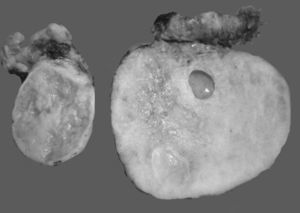

En algunos casos es difícil distinguir si se trata de un tumor primario de ovario o metastásico. Esto especialmente ocurre con el cáncer de colon, en el cual se describe que el 45% de los tumores metastásicos de colon a ovario se diagnostican previamente como primarios de ovario. Las metástasis de adenocarcinoma de colon son los tumores que simulan con mayor frecuencia un carcinoma primario de ovario, estimándose que del 10 al 30% de las mujeres con carcinoma de colon presentarán focos tumorales secundarios en el ovario1,2,13,20,21. A simple vista son indistinguibles del carcinoma ovárico primario, y en el examen macroscópico se ve que en muchas ocasiones simulan un cistadenocarcinoma primario del ovario22,23, tal como se muestra en la figura 1.

Fotos comparativas de una neoplasia mucinosa primaria de ovario (a) y un adenocarcinoma mucinoso metastásico a ovario (b). A simple vista no es posible distinguir entre una neoplasia primaria y una metastásica, ya que ambas son de gran tamaño, multiloculares y con presencia de abundante mucina.